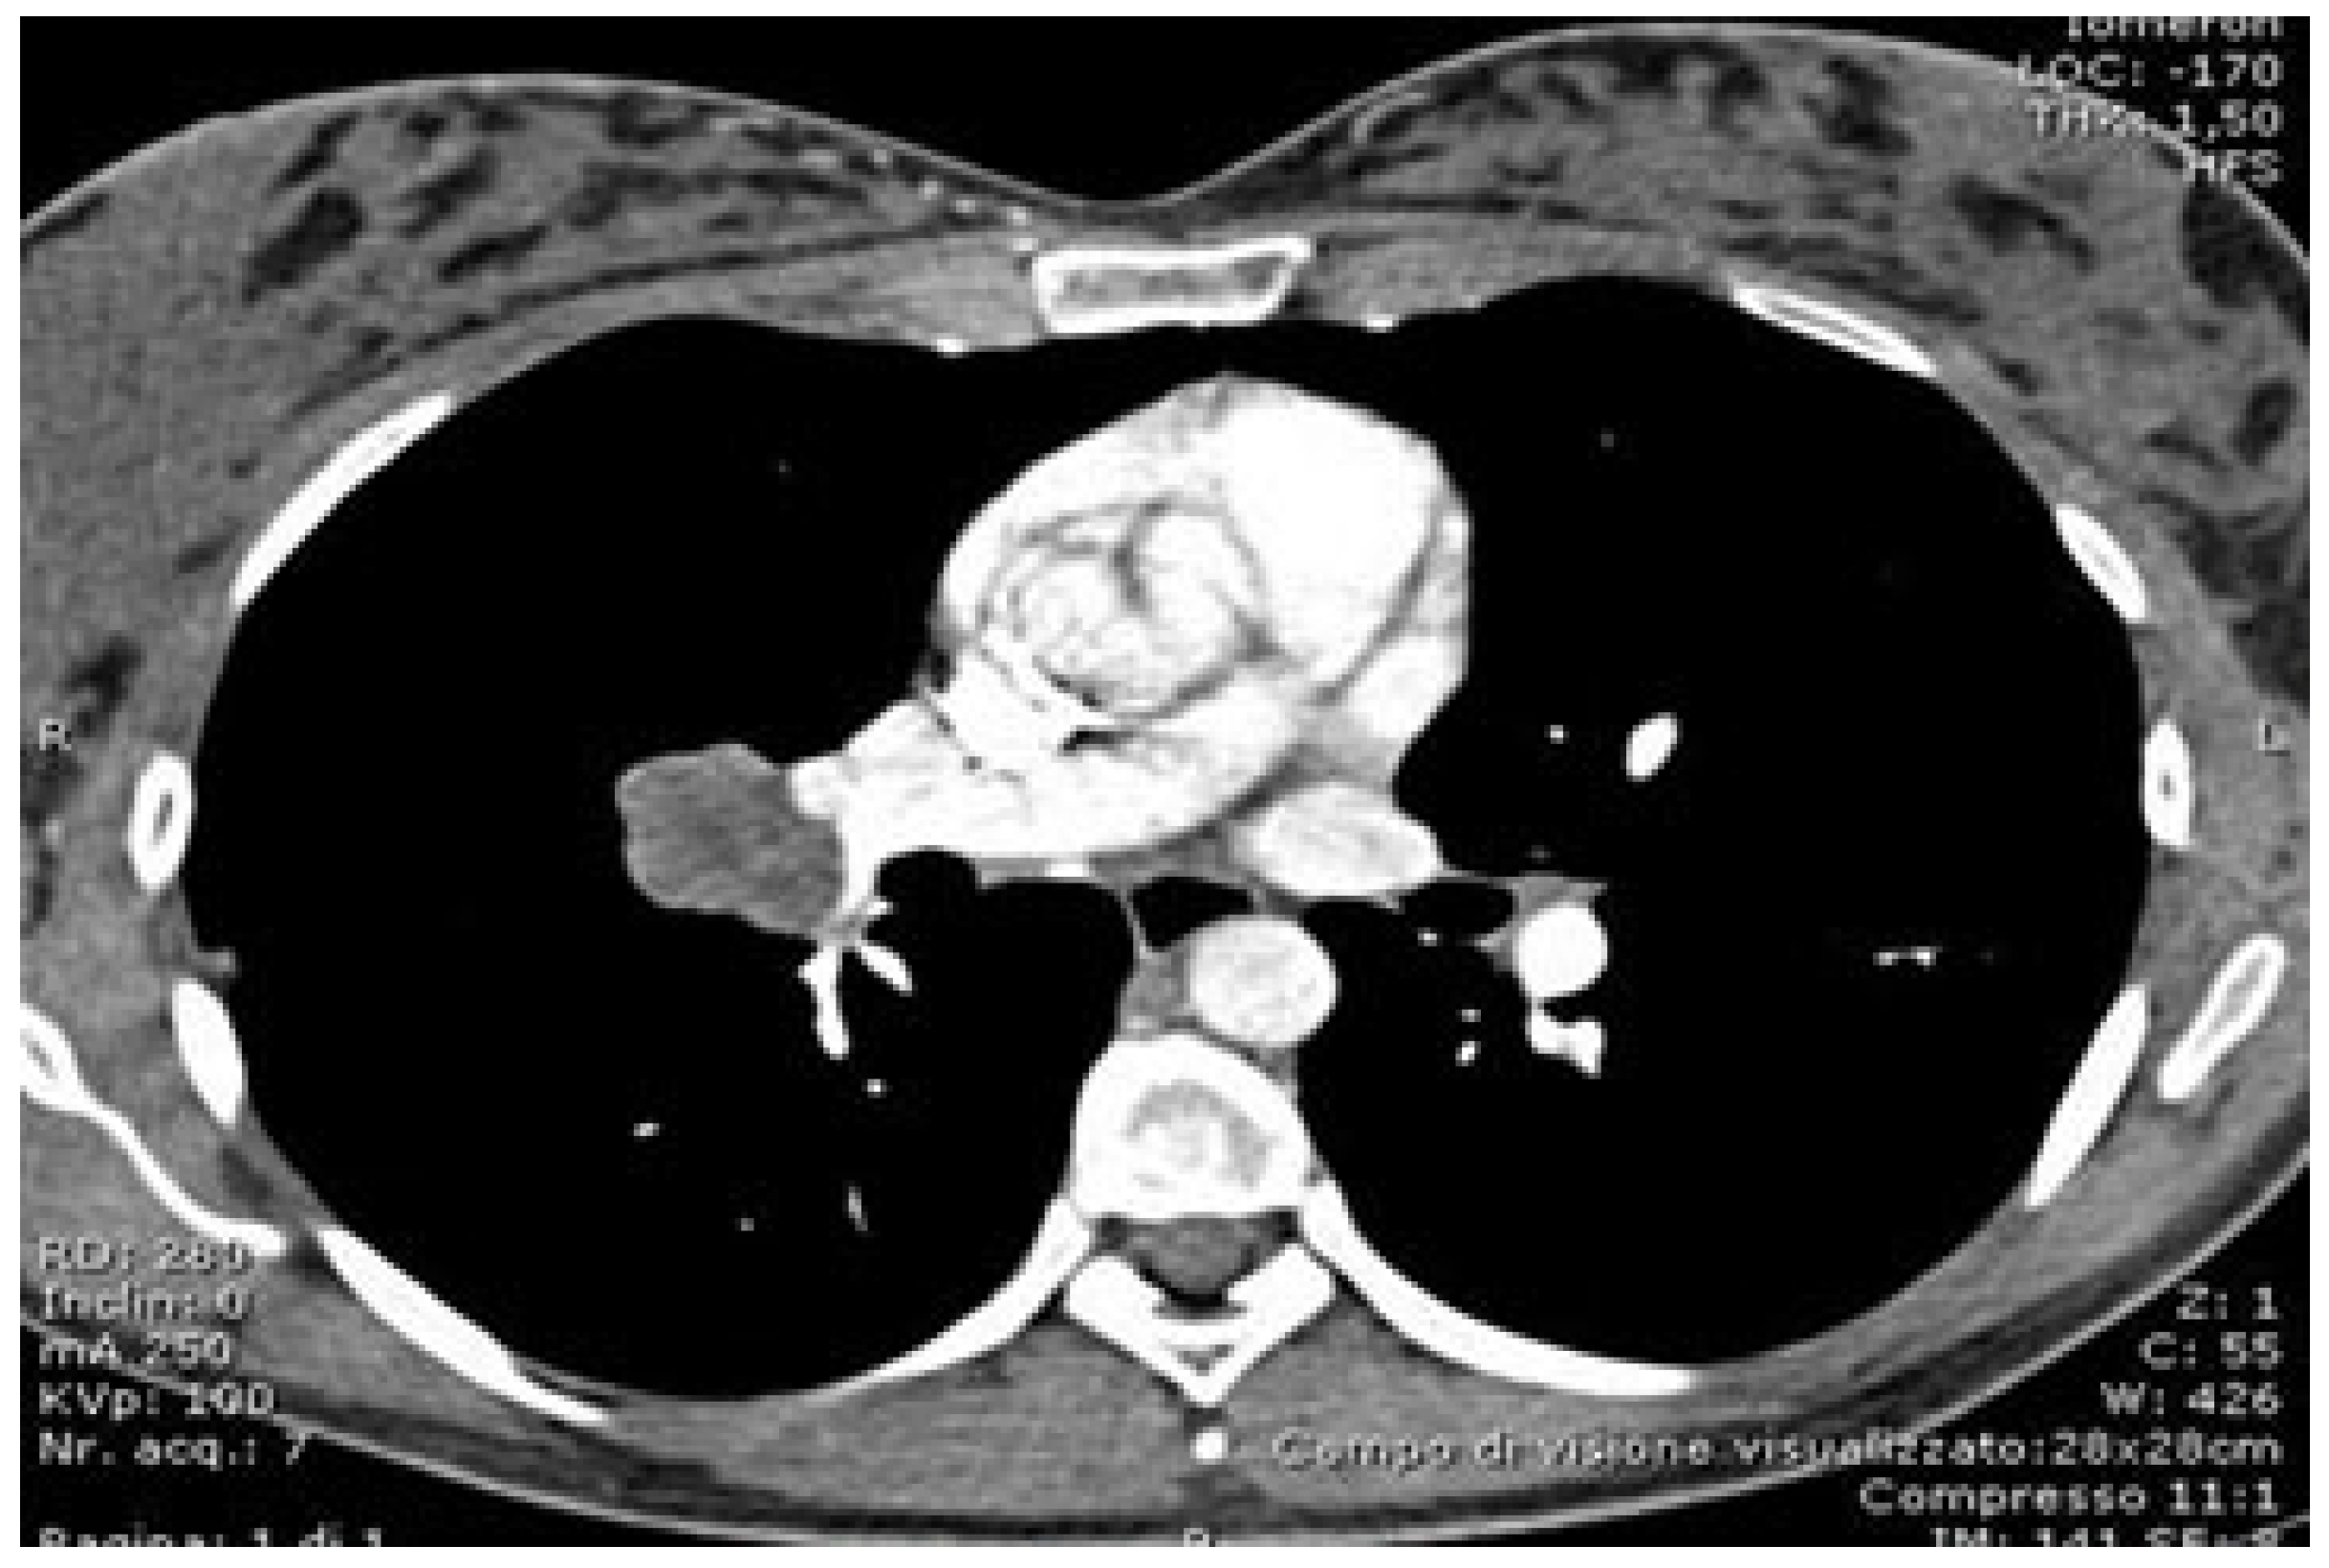

- Ikeda, N.; Yoshimura, A.; Hagiwara, M.; Akata, S.; Saji, H. Three dimensional computed tomography lung modeling is useful in simulation and navigation of lung cancer surgery. Ann. Thorac. Cardiovasc. Surg. 2013, 19, 1–5. [Google Scholar] [CrossRef] [PubMed]

- Chen-Yoshikawa, T.F.; Date, H. Update on three-dimensional image reconstruction for preoperative simulation in thoracic surgery. J. Thorac. Dis. 2016, 8 (Suppl. S3), S295–S301. [Google Scholar] [CrossRef]